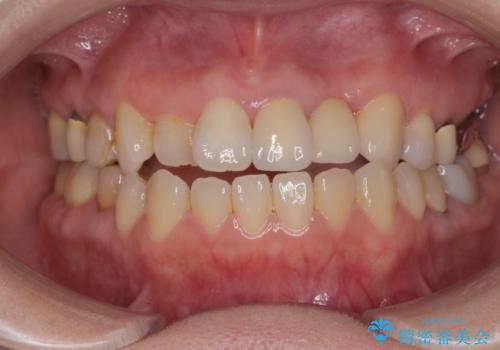

左上2は、クラウン メタルコアの除去を行ったところ虫歯の再発や亀裂を認め、長期的な予後の期待が難しいことから抜歯を行い

ブリッジで審美性の回復を行っていく運びとなりました。

精度、周囲の歯の色調にこだわったオールセラミックブリッジを作製し、しっかりと機能・審美性を改善することができました。